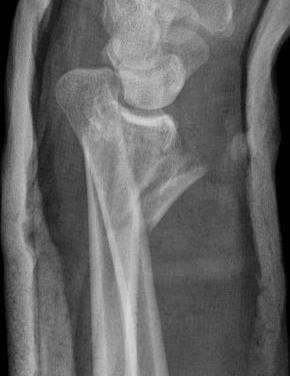

DRUJ instability without ulna styloid fractures

Incidence

Omokawa et al J Wrist Surg 2014

- ORIF 346 unstable distal radius fractures

- 6% had unstable DRUJ after ORIF

- treated with open dorsal radio-ulna ligament repair

Fujitano et al J Hand Surg Am 2011

- ORIF 163 unstable distal radius fractures

- 7% had unstable DRUJ after ORIF

Etiology

Lindau et al J Hand Surg Am 2000

- 51 displaced distal radius tears patients < 60

- arthroscopy demonstrated TFCC tears 84%

- 10/11 complete peripheral TFCC tears had DRUJ instability at follow up